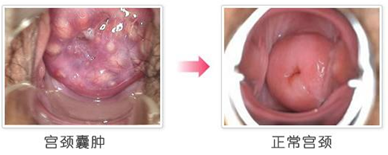

宫颈囊肿和我们平常所说的卵巢囊肿等囊肿是不一样的。它主要是由宫颈糜烂在愈合过程中,子宫颈表面的上皮不断生长,并覆盖在子宫颈表面,使腺管开口堵塞,分泌物不能外流而潴留在里面,所形成的囊肿。宫颈囊肿表现出来的症状有额是很明显的,那么具体会有哪些症状呢?

宫颈囊肿的早期症状并不明显,所以对具体症状要有所了解,才能发现疾病。